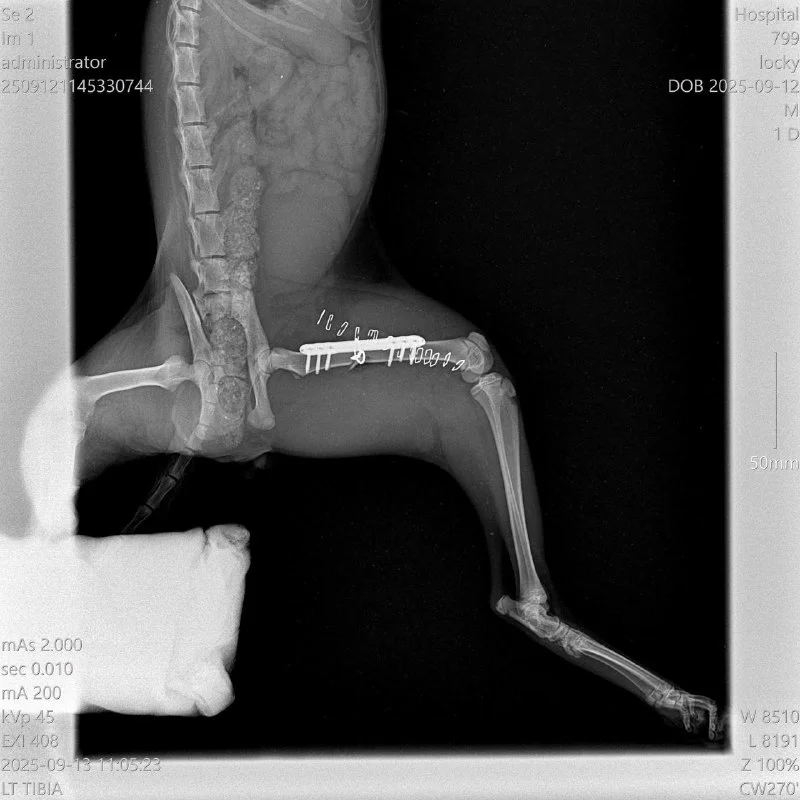

Неделю назад в пятницу 12/09 мне написала Биляна - с просьбой помочь отвезти рыжего кота со сломанной лапой в клинику.

Отнесли к Мариносу. По рентгену видно, что перелом сложный, но доктор сработал профессионально и оперативно (не зря говорят, что в плане хирургии у Мариноса - золотые руки!) и теперь у котика титановая пластина в лапке, благодаря которой сращивается кость 💙 🐾

Котик молодой, ему нет и года - но реабилитация такого сложного перелома - это 4-6 недель, в которых надо ограничить движение.

В эту субботу 20/09 мы поехали в клинику, сняли швы и поставили первую комплексную вакцину трикэт.